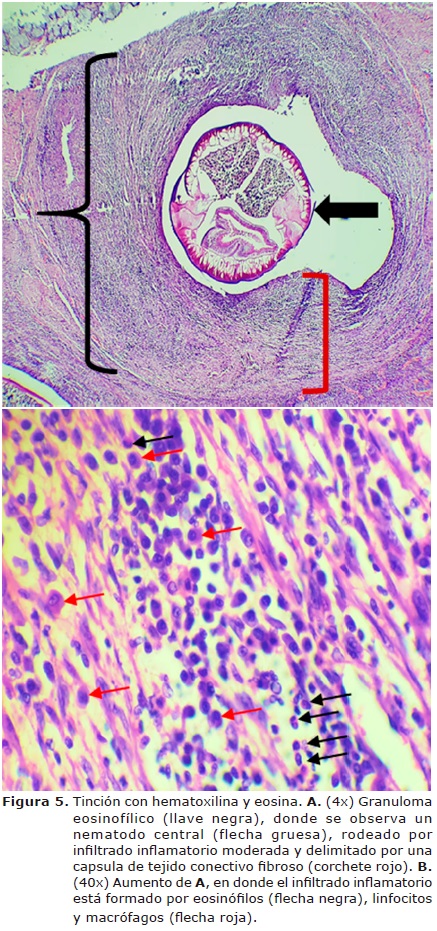

Se revisaron secciones de tejido identificadas como nódulo de esófago, en donde se observó un granuloma eosinofílico, caracterizado porque en su centró se encontró una estructura parasitaria consistente con un nematodo, rodeado por un infiltrado inflamatorio severo formado por neutrófilos, eosinófilos, linfocitos, células plasmáticas y macrófagos; los cuales se encuentran delimitados por una cápsula de tejido conectivo fibroso formada por gran cantidad de fibroblastos, fibrocitos y fibras de colágena (Figura 5).

Durante la necropsia del perro se observaron tres nódulos en el esófago que durante la incisión de la masa permitió visualizar nematodos adultos de S. lupi. En el estudio histológico se observó en los nódulos con granuloma eosinofílico, con presencia del nematodo rodeado por un infiltrado inflamatorio severo por neutrófilos, eosinófilos, linfocitos, células plasmáticas y macrófagos. Estos hallazgos coinciden con lo reportado por Diakou et al (25) quienes describen que los granulomas consisten en un área central que se encuentran rodeado de eosonófilos degenerados y viables, así como la infiltración de neutrófilos como parte de la respuesta inmune del animal. Asimismo, estos se encuentran delimitados por tejido conectivo infiltrado predominantemente por células mononucleares, específicamente histiocitos, células plasmáticas y linfocitos.